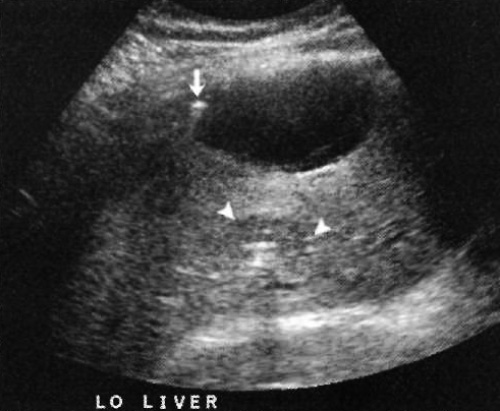

Характерные ультразвуковые признаки пиогенного абсцесса печени отсутствуют. Визуализируют гипо- или анэхогенные образования, которые примерно в 50% случаев образуют акустический эффект усиления. Если в абсцессе есть газы, образование становится эхогенным с нечетким затенением и плохим контурированием границ (фото 8):

Фото 8. Абсцесс печени. Визуализируется кистозное образование с наличием эхогенных очагов, стрелкой обозначено скопление газа. Указателями обозначен более плотный вид абсцесса меньшего размера, который расположен позади